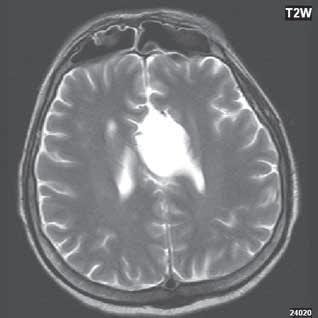

Heterotopie šedé hmoty (subependymální forma) (šipka)

Obr. I.1.3c Heterotopie šedé hmoty (subependymální forma) (šipka)

Obr. I.1.3d Heterotopie šedé hmoty (subependymální forma); stejný pacient jako na obr I 1 3c

Zobrazení

CT je modalita málo senzitivní, prokáže ložiska denzity šedé hmoty mozkové, beze změn po aplikaci KL. MR je nejcitlivější zobrazovací metoda (optimální zobrazení šedé hmoty mozkové je technikou T1W + IR, naopak modalita FLAIR, velmi citlivá pro zobrazení změn bílé hmoty mozkové, nemá u heterotopie změny signálu nebo jen velmi diskrétní). Signálově ložiska heterotopie odpovídají šedé hmotě mozkové. Po aplikaci KL je beze

změn. Při ložiskové, subkortikální lokalizaci může být mozková kůra v jejich blízkosti zesílena, s projevy kortikální dysplazie.